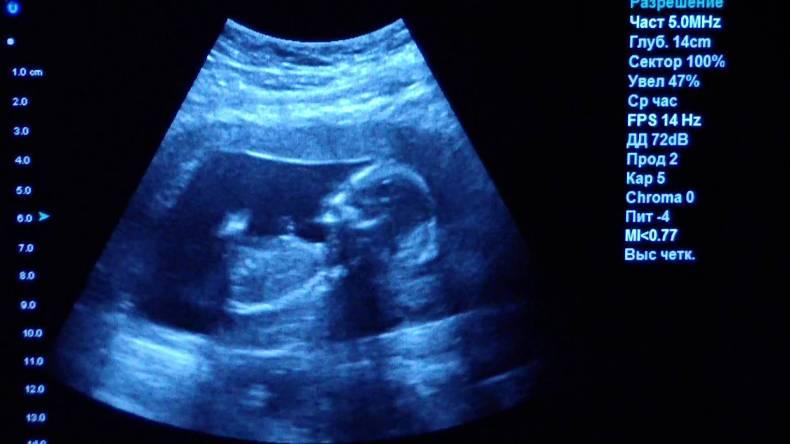

Ультразвуковое исследование (УЗИ)

Рентгенография — не единственный способ “заглянуть внутрь” человеческого тела, ещё одна технология — ультразвук. Звуковые волны используют для ориентации в пространстве некоторые животные, например, летучие мыши. Люди тоже научились использовать волны для решения некоторых задач, в том числе и в медицине. Картинку внутренних органов можно получить, если направить звуковую волну в тело человека и проследить за её возвращением. Компьютер помогает обработать результаты и представить их в виде трёхмерной картинки.

Главное преимущество такого способа исследования — безопасность. УЗИ можно делать даже беременным женщинам, кроме того, приборы УЗИ-приборы мобильны, их легко можно поставить в палате пациента, чтобы наблюдать за состоянием органов и кровотока в режиме реального времени.

Однако УЗИ не может обеспечить картинку высокой чёткости, поэтому использование этого метода исследование ограничено, например, при помощи УЗИ нельзя диагностировать заболевания ЖКТ.

УЗИ